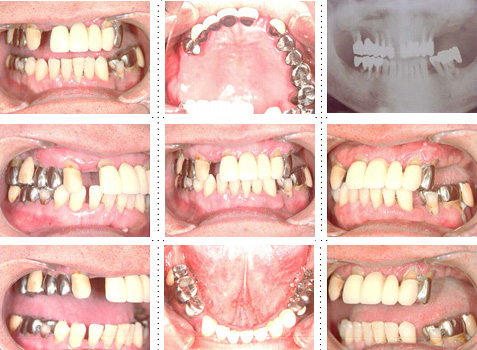

症例1

58才 女性

嘔吐反応が激しく入れ歯を入れると気持ち悪くなってしまうと、インプラント希望で来院されました。

上顎左右奥に4本ずつ計8本のインプラント埋入。下顎左右奥に3本ずつ計6本のインプラント埋入上下顎とも全体的にセラミックを使用した冠をセット。